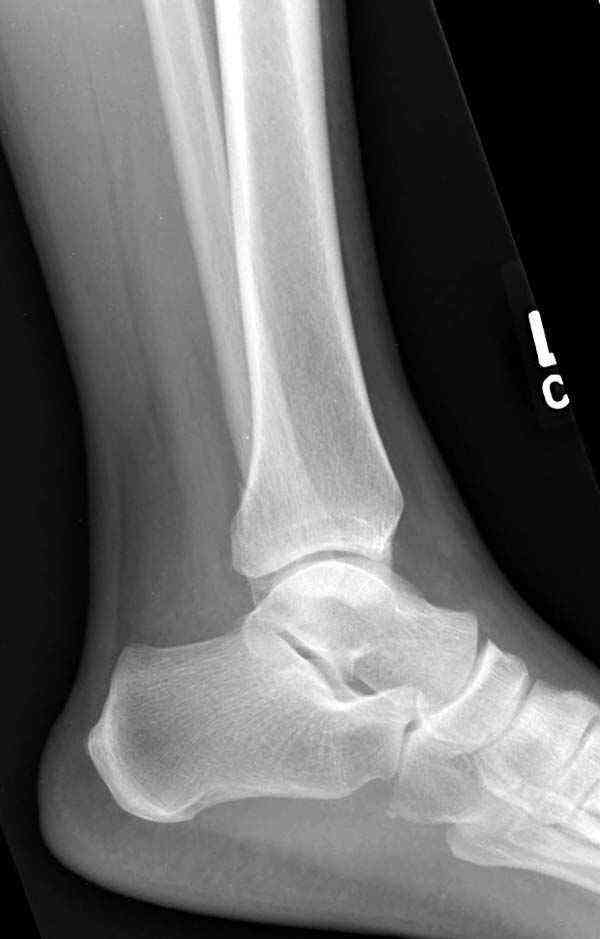

Добрый вечер, коллеги! Хотелось бы увидеть стандартные проекции, прямо, боком и мортиз. Дело скорее всего не в пластине. Стяжка скорее всего не дотянута изначально. Отсюда игра синдесмоза и прорезывание проволоки Вебера. Вообще то стоило бы делать по классике , а именно : Наружная лодыдка - противоскользящая плата по Веберу, над синдесмозом - два позиционных винта ( это "ключи" сустава) внутренняя лодыжка - можно и проволокой, но при адекватной фиксации латерального комплекса.

Визуально никаких вопросов по репозиции не было.Да и на основании чего сомнения,что наружная лодыжка не полностью репонирована или прорезалась проволка ???Я не вижу...Снимок после репозиции справа.

Раз ,есть желание посмотреть другую проекцию выкладываю-ну лучшего качества нет...

Коллеги правы, что при рутинных переломах достаточным бывает обычные снимки с мортизом. А стрессовые рентгенограммы могут уточнить, есть ли разрыв синдесмоза.